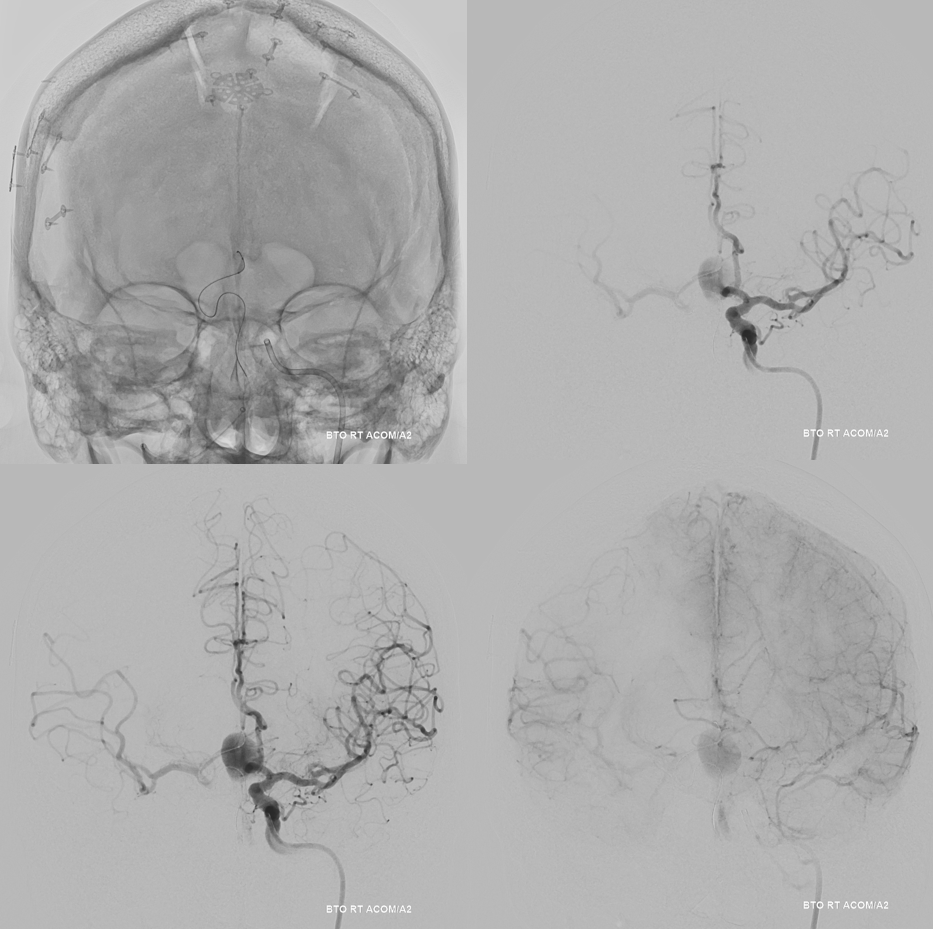

Angio intraop post bypass- STA-MCA working

ACA-ACA did not have flow at this point. Tested by a left A2 BTO. How does that test for bypass patency?

STA-MCA bypass, right ophthalmic, and right PCOM not enough to supply right ACA at this stage — tested by left supraclinoid bypass — what is the rationale there?

Now we decided to wait a few months

Bypass working even better

PCOM working correspondingly less. Ophthalmic no longer needed

Bilateral CBCT Injections. A big bonus — the ACA-ACA bypass now seems to be patent! Cant see that from 2D images really at this stage. We did not realise this at first but became clear later

A3-A3 bypass more images